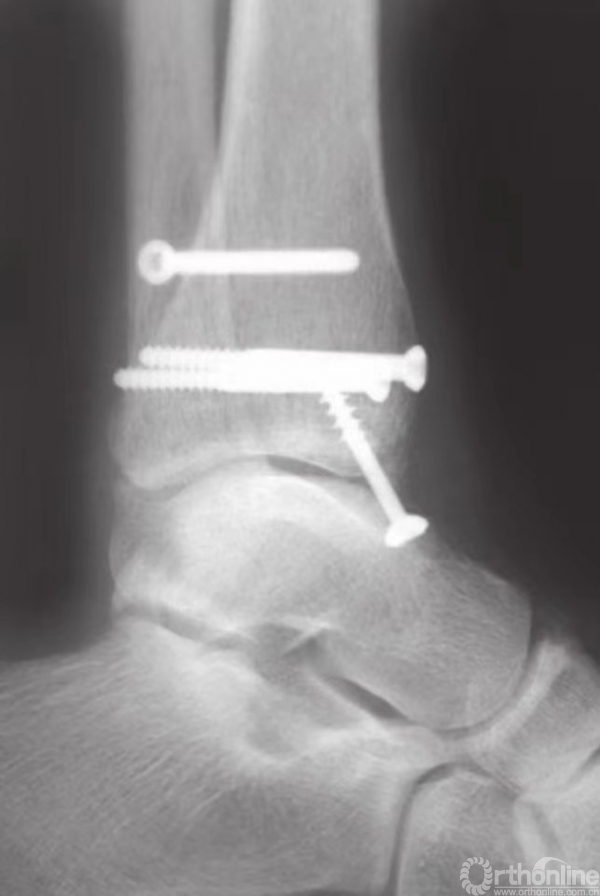

内踝固定技术

在内踝开直切口或略呈弧形的切口。根据皮肤的状况,内侧骨折片的大小,以及是否需要固定后踝,弧线可向前或向后延伸。弧形切口有助于固定内侧嵌入性骨折,也有助于治疗关节内有游离骨块的骨折。另外,因为可能引起伤口裂开,故应避免在内踝高骨开直切口。

在钳的前方和后方,放置两枚较小的克氏针,并使之与骨折线垂直(图15)。注意要保证克氏针不刺穿踝关节(图16)。为防止刺穿关节,可将角度调至与水平方向约成30°。在克氏针上方和对侧皮质附近,使用管状钻钻孔。后嵌入4mm部分有螺纹的空心松质骨螺钉。

在骨折片尖部固定螺钉时,三角韧带表层可能会部分劈裂。再将另一枚螺钉以相同方式嵌入(图17),无需涉及对侧皮质。在大多数病例中,40或45mm长度规格的螺钉可以起到很好的固定作用。这些螺钉应相互平行,并在内踝骨折片上方铺开,以便更好地控制旋转(图18)。

图17 半螺纹松质骨空心钉最终固定骨折

图18 内踝固定完成

通过X线透视确认骨折复位和螺钉的固定(图19)。用可吸收缝线缝合较薄的皮下层后,再将皮肤缝合。